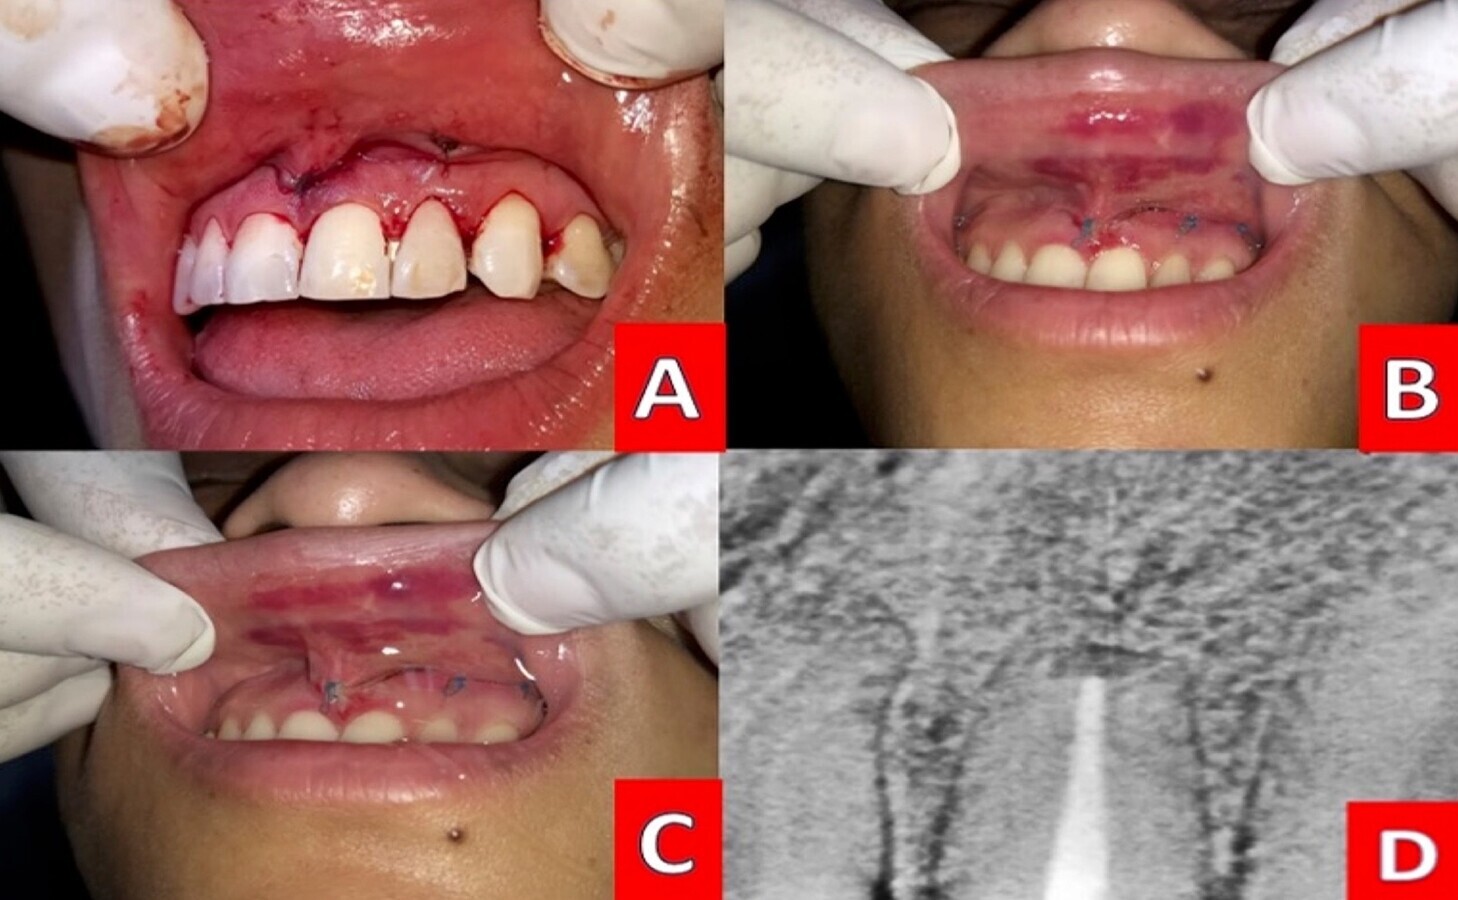

Figura 5. A) Sutura con nylon 3-0. B-C) Valoración una semana después adicionando terapia con gel de quitosan. Retiro de sutura a los 21 días. D) Seguimiento radiográfico a los seis meses

Se procedió a confrontar los tejidos suturando con nylon 5-0 y se indicó terapia farmacológica oral con amoxicilina de 500 mg e ibuprofeno de 600 mg, terapia adicional con gel de quitosan. Se extendieron indicaciones de dieta y cuidados. La paciente no reporto malestar, retirando la sutura 21 días posterior a la intervención. Seis meses después hubo un control radiográfico observando franca recuperación del periápice (Figura 5).